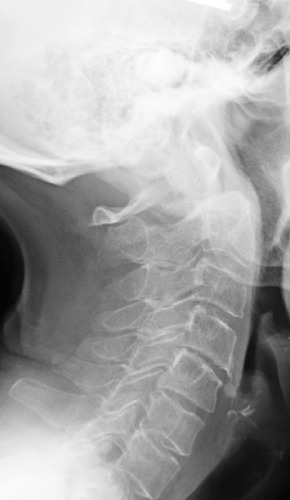

1. What is the key finding?

2. What is the etiology of the main finding - trauma, congenital, other?